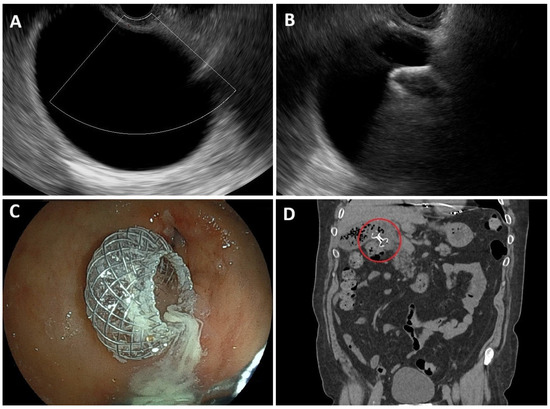

Endoscopic Ultrasound-Guided Lumen-Apposing Metal Stent Drainage in Benign Pancreatobiliary and Gastrointestinal Disease: Evolving Techniques and Clinical Outcomes

Interventional endoscopic ultrasound (EUS) has become a cornerstone in the management of malignant pancreatobiliary diseases, offering minimally invasive alternatives to traditional surgical approaches. More recently, accumulating evidence supports its expanding role in the treatment of benign pancreatobiliary conditions, including acute cholecystitis and pancreatitis, [...] Read more.

Interventional endoscopic ultrasound (EUS) has become a cornerstone in the management of malignant pancreatobiliary diseases, offering minimally invasive alternatives to traditional surgical approaches. More recently, accumulating evidence supports its expanding role in the treatment of benign pancreatobiliary conditions, including acute cholecystitis and pancreatitis, benign gastric outlet obstruction, and scenarios involving altered gastrointestinal anatomy. This narrative review provides an overview of key EUS-guided drainage techniques utilizing lumen-apposing metal stents (LAMSs) in benign settings. It focuses on procedures such as EUS-guided gallbladder drainage, drainage of abdominal collections, EUS-directed transgastric ERCP (EDGE), and EUS-gastroenterostomy. These interventions have demonstrated high technical and clinical success rates, favorable safety profiles, and expanding indications, particularly among patients who are poor surgical candidates. This review highlights evolving techniques, clinical outcomes, and the impact of device innovations on procedural efficacy and safety. Full article